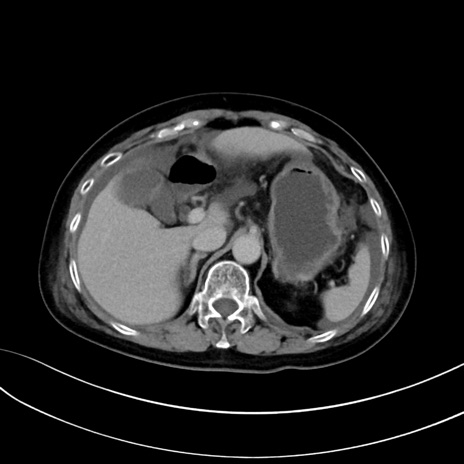

症例13 CT(横断像)1日半後